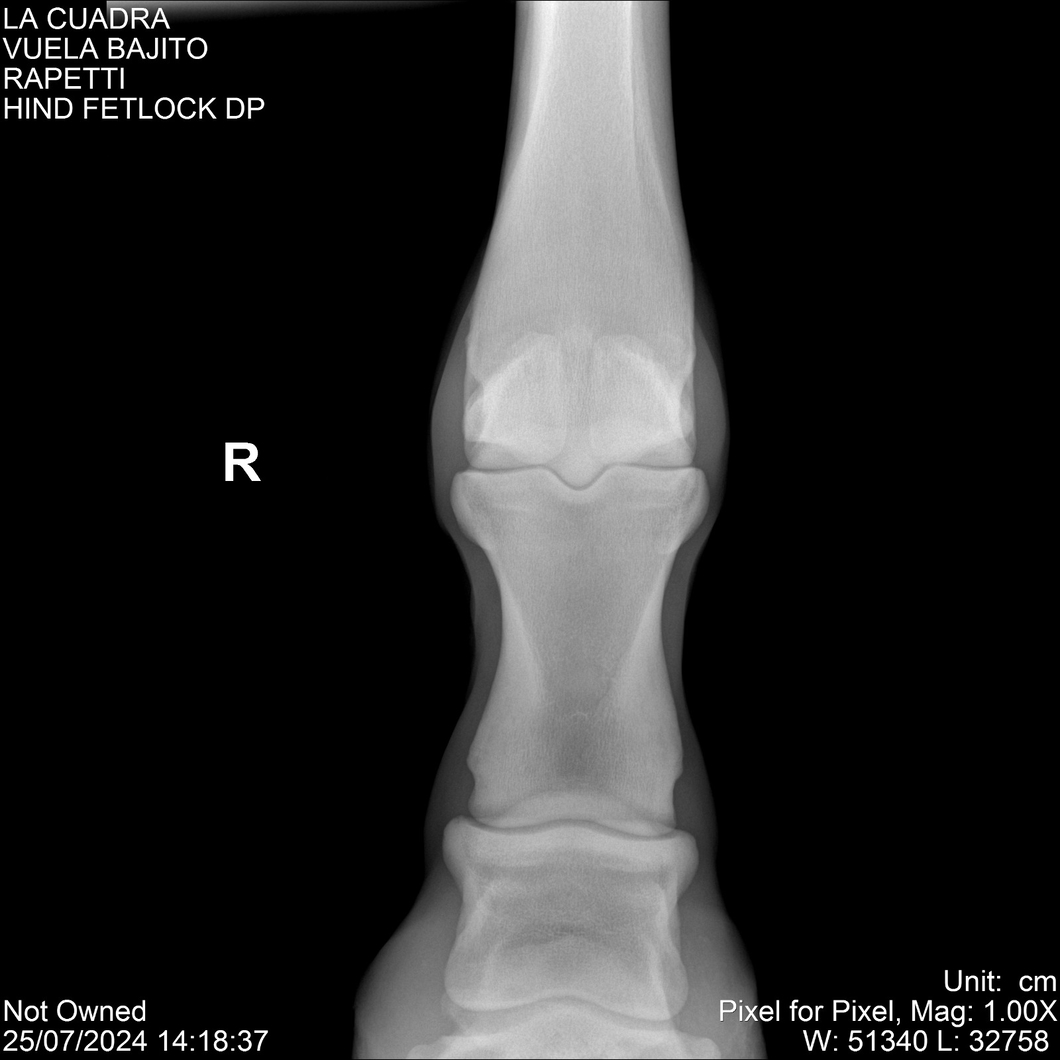

LOTE 16, VUELA BAJITO Lote Anterior Volver al remate Lote Siguiente Ficha Contacto Montevideo - Ficha del Lote Identificador: #284451 Categoría: Yeguarizos Montevideo - 77 Visualizaciones ClicData Contacto Empresa: Abelenda N. R., Walter Hugo Nombre*: Teléfono* : E-mail* : Mensaje Enviar Registrese gratis Este contenido Exclusivo está disponible sólo para usuarios registrados Ingresar